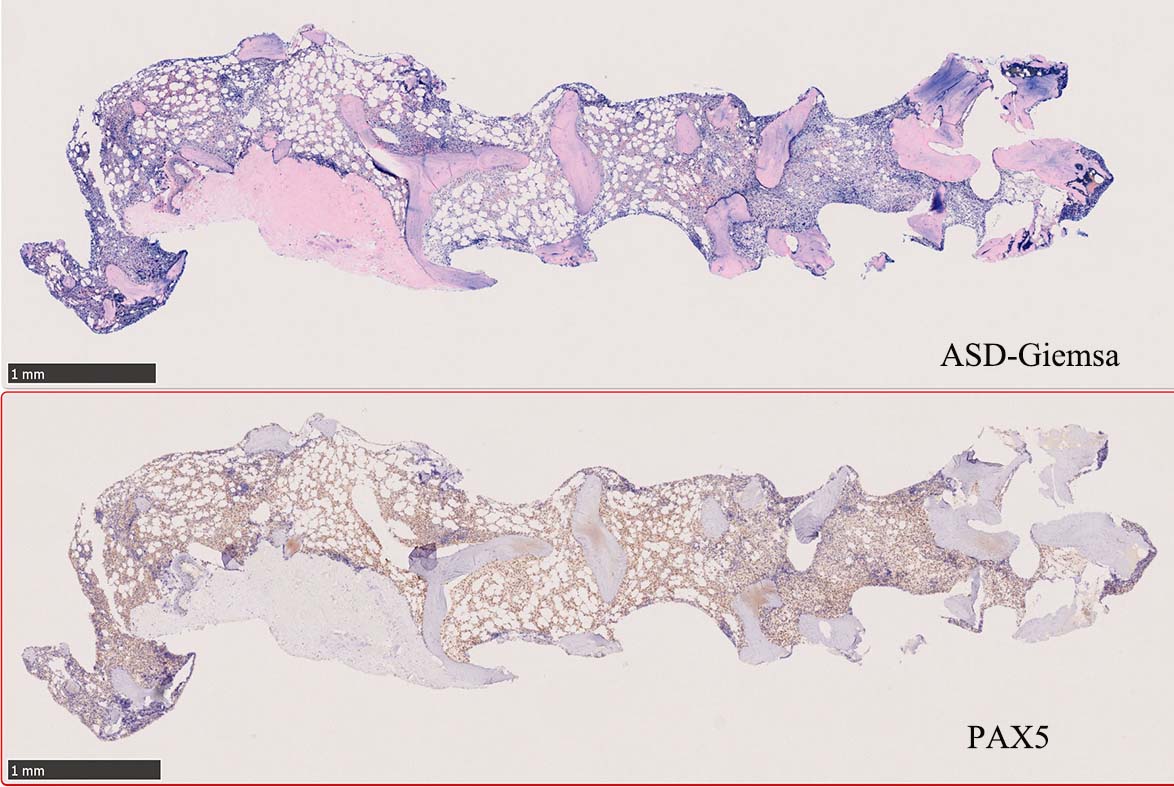

ASD-G 低倍率所見では赤芽球血島は幼若赤芽球の集簇巣が散在する, 顆粒球系細胞(ASDに赤く染色される)は減少,granulopoietic hypoplasiaを呈する.疎な集簇を示すmast cellsの増加がある.

ASD-G陰性の細胞がびまん性に増加しているように見える.

ASD-Giemsa陰性の細胞がシート状に増殖する. 核はクロマチン濃染, 核小体は不明瞭.類円形, 卵円形, くびれを持つ多稜形核, 長円形いびつで屈曲した核, など多彩. 細胞質は淡清色調, 広く淡明. 赤芽球血島は幼若赤芽球のみで形成される異形成像を示す. やや離れて成熟赤芽球が疎な集簇を示す.

Ag染色では, 疎な弾性線維が増生し,増殖細胞を小胞巣状に分画するいわゆる「lymphomatoid pattern」を呈する. 本例では, Mgkに異形成所見がある.

Hairy-FCM のコピー.jpg ASD-up-PAX5ok.jpg びまん性にPAX5陽性の小型B-cellsが増殖している.

増殖細胞はCD20(相変わらずべったり染まる), CD19, PAX5陽性 CD25陽性.